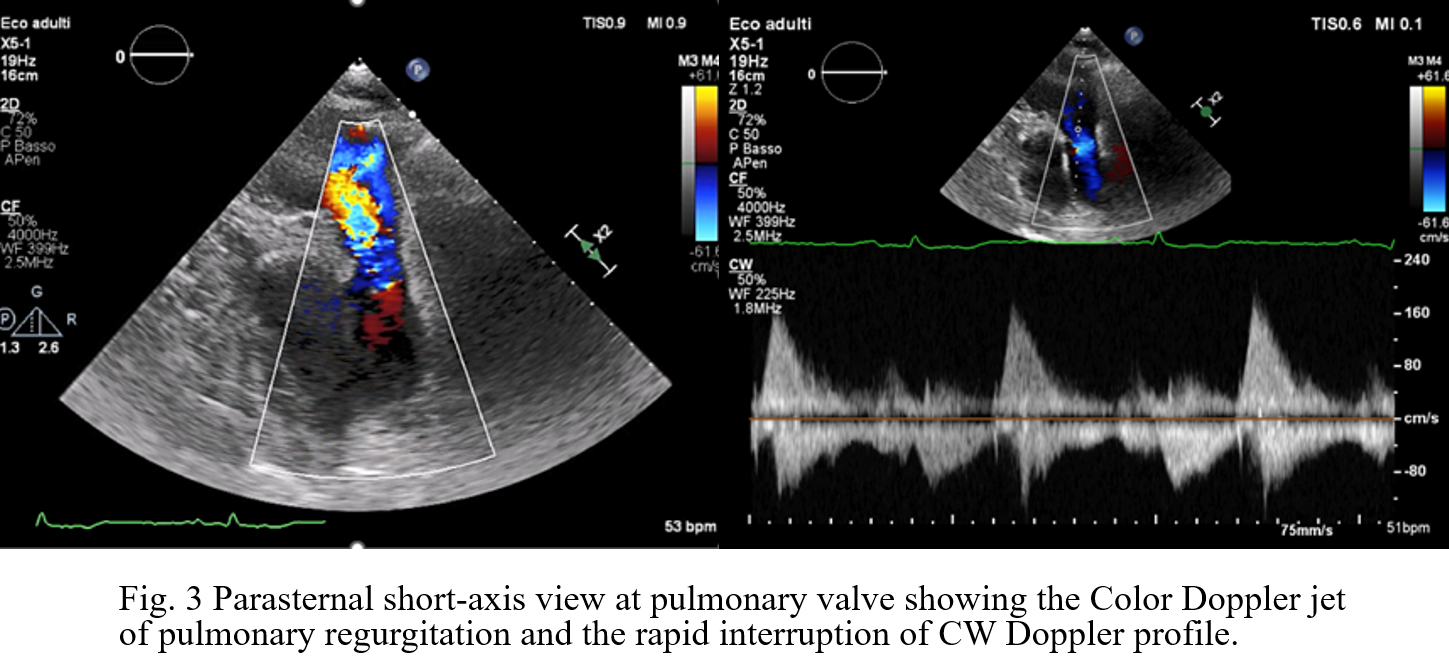

Background: Carcinoid Heart Disease (CHD) is a rare but ominous complication of neuroendocrine tumors (NETs), characterized by fibrotic plaque deposition on endocardial surfaces. While tricuspid valve involvement is well-documented, the pulmonary valve is often overlooked despite its significant impact on right ventricular (RV) hemodynamics. Case Presentation: A 73-year-old male with an ileal NET and liver/peritoneal metastases, stable under lanreotide acetate for four years, presented with progressive dyspnea and peripheral edema. Initial transthoracic echocardiography (TTE) and cardiac MRI identified severe tricuspid regurgitation (TR) and significant right heart dilation. The patient was referred to our Department to explore the feasibility of transcatheter tricuspid intervention. Advanced Imaging Findings: Comprehensive TTE and transesophageal echocardiography (TEE) confirmed RV dilation (RVD1 49 mm, RVOT 44 mm) with preserved systolic function (TAPSE 22 mm, FAC 48%). The tricuspid valve exhibited classic CHD features: fibrotic, retracted, and rigid leaflets with commissural fusion. 3D echocardiography showed a fixed, oval-shaped orifice (1.6 cm²) that remained immobile throughout the cardiac cycle due to systolic-diastolic mobility restriction (Fig.1). This resulted in massive TR (VC 16 mm, ERO 1.6 cm², dense triangular CW Doppler profile and systolic flow reversal in suprahepatic veins, Fig.2) combined with tricuspid stenosis (mean gradient 5 mmHg). Crucially, detailed evaluation of the pulmonary valve revealed retracted cusps. Diagnosis of pulmonary regurgitation (PR) was challenging at Color Doppler but a multiparametric assessment detected severe PR (dense CW Doppler with rapid interruption due to a rapid rise of RV diastolic pressures with pressure half-time of 80 msec and PR index of 0,62, Fig.3). Conclusion: These findings are pathognomonic for CHD, where vasoactive substances (e.g., serotonin) induce endocardial fibrosis. In this case, the complex anatomy of the tricuspid valve, combined with significant pulmonary valve involvement, rendered the patient unsuitable for transcatheter correction. This case emphasizes that the pulmonary valve must be rigorously evaluated in CHD, with a multiparametric approach, as its involvement is a critical determinant of surgical vs. percutaneous strategy. Management in this case must involve a multidisciplinary Heart Team to balance surgical risks against oncological prognosis.